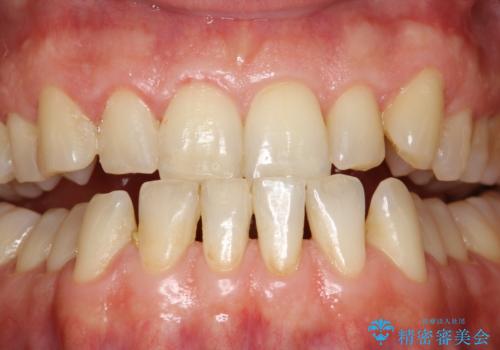

歯磨き中に血が出る PMTCで歯石除去

- 毎日の歯磨きの際に出血する。歯科でにクリーニンングをしばらくしていないとのことでした。PMTC60分コースを行いました。

歯磨きの際の出血は、歯肉炎や歯周病の症状とも言えます。歯周ポケットに歯周病菌が棲みつき、歯周病菌の出す毒素が歯茎に炎症を起こします。炎症が拡大し、歯周組織が破壊されたまま放置すると、最悪の場合、歯を支えている骨が溶かされ、歯がぐらぐらしてきます。

そのため重要なのが、毎日の歯磨きで可能な限り汚れを取り除くこと・定期的に歯科医院で歯周病の検査をしたり、歯石除去や歯茎の炎症を取り除くことです。